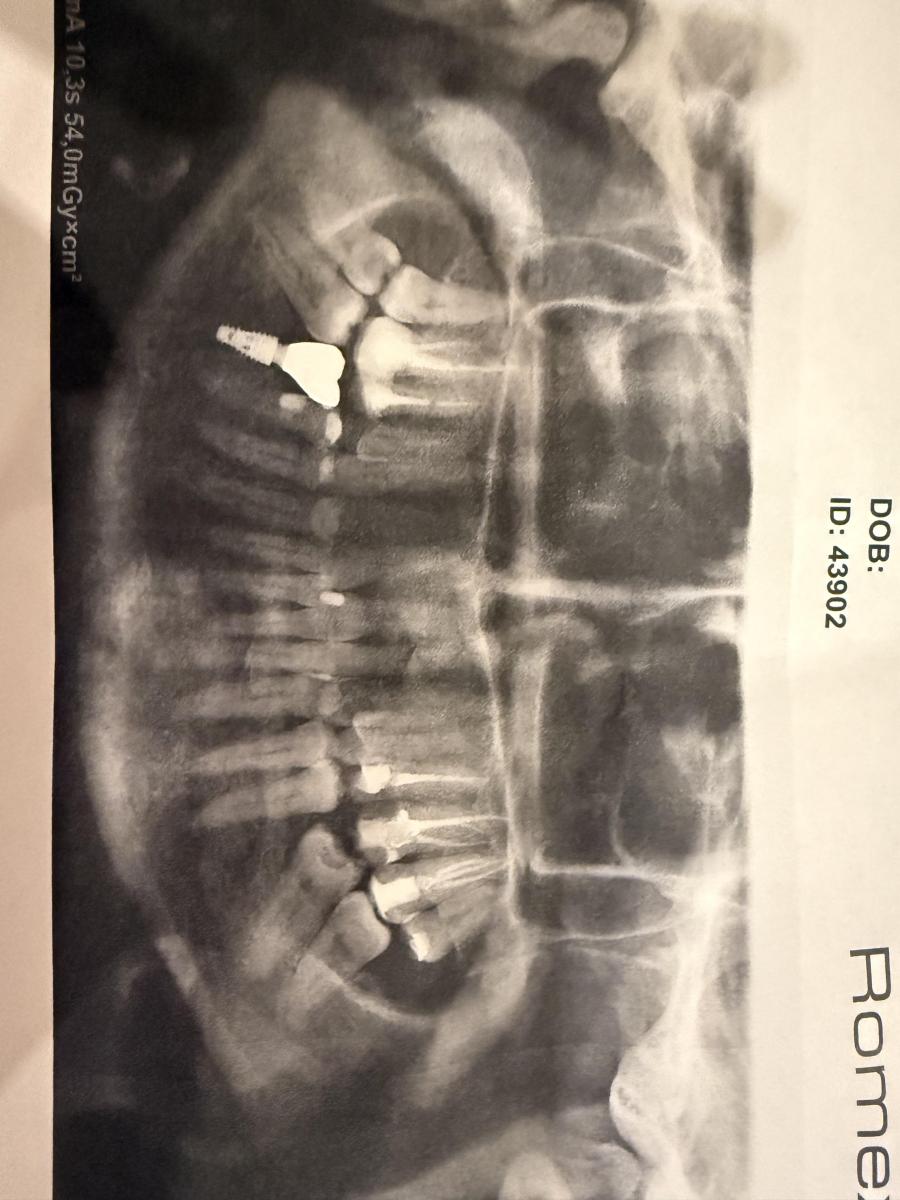

Перелечила зубы для коронок, сейчас поставили штифт и временные коронки, зубы ноют ужасно. Может видно что либо по снимку.

Думаю надо полечить 48...

Юрий Жигурт, может есть смысл сделать кт и посмотреть, что с 15 и 16,и пока не устанавливать постоянную коронку? Так как ноют эти зубы как при перидонтите, был уже опыт с ним на 25 зубе